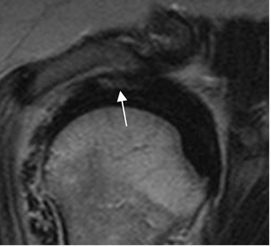

Fig 138. Tendinitis crónica reagudizada del supraespinoso.

RM sagital en T2. Tendón del supraespinoso engrosado por patología crónica. Hacia la superficie bursal hay zona hiperintensa, por tendinitis o ruptura parcial. (Flecha).